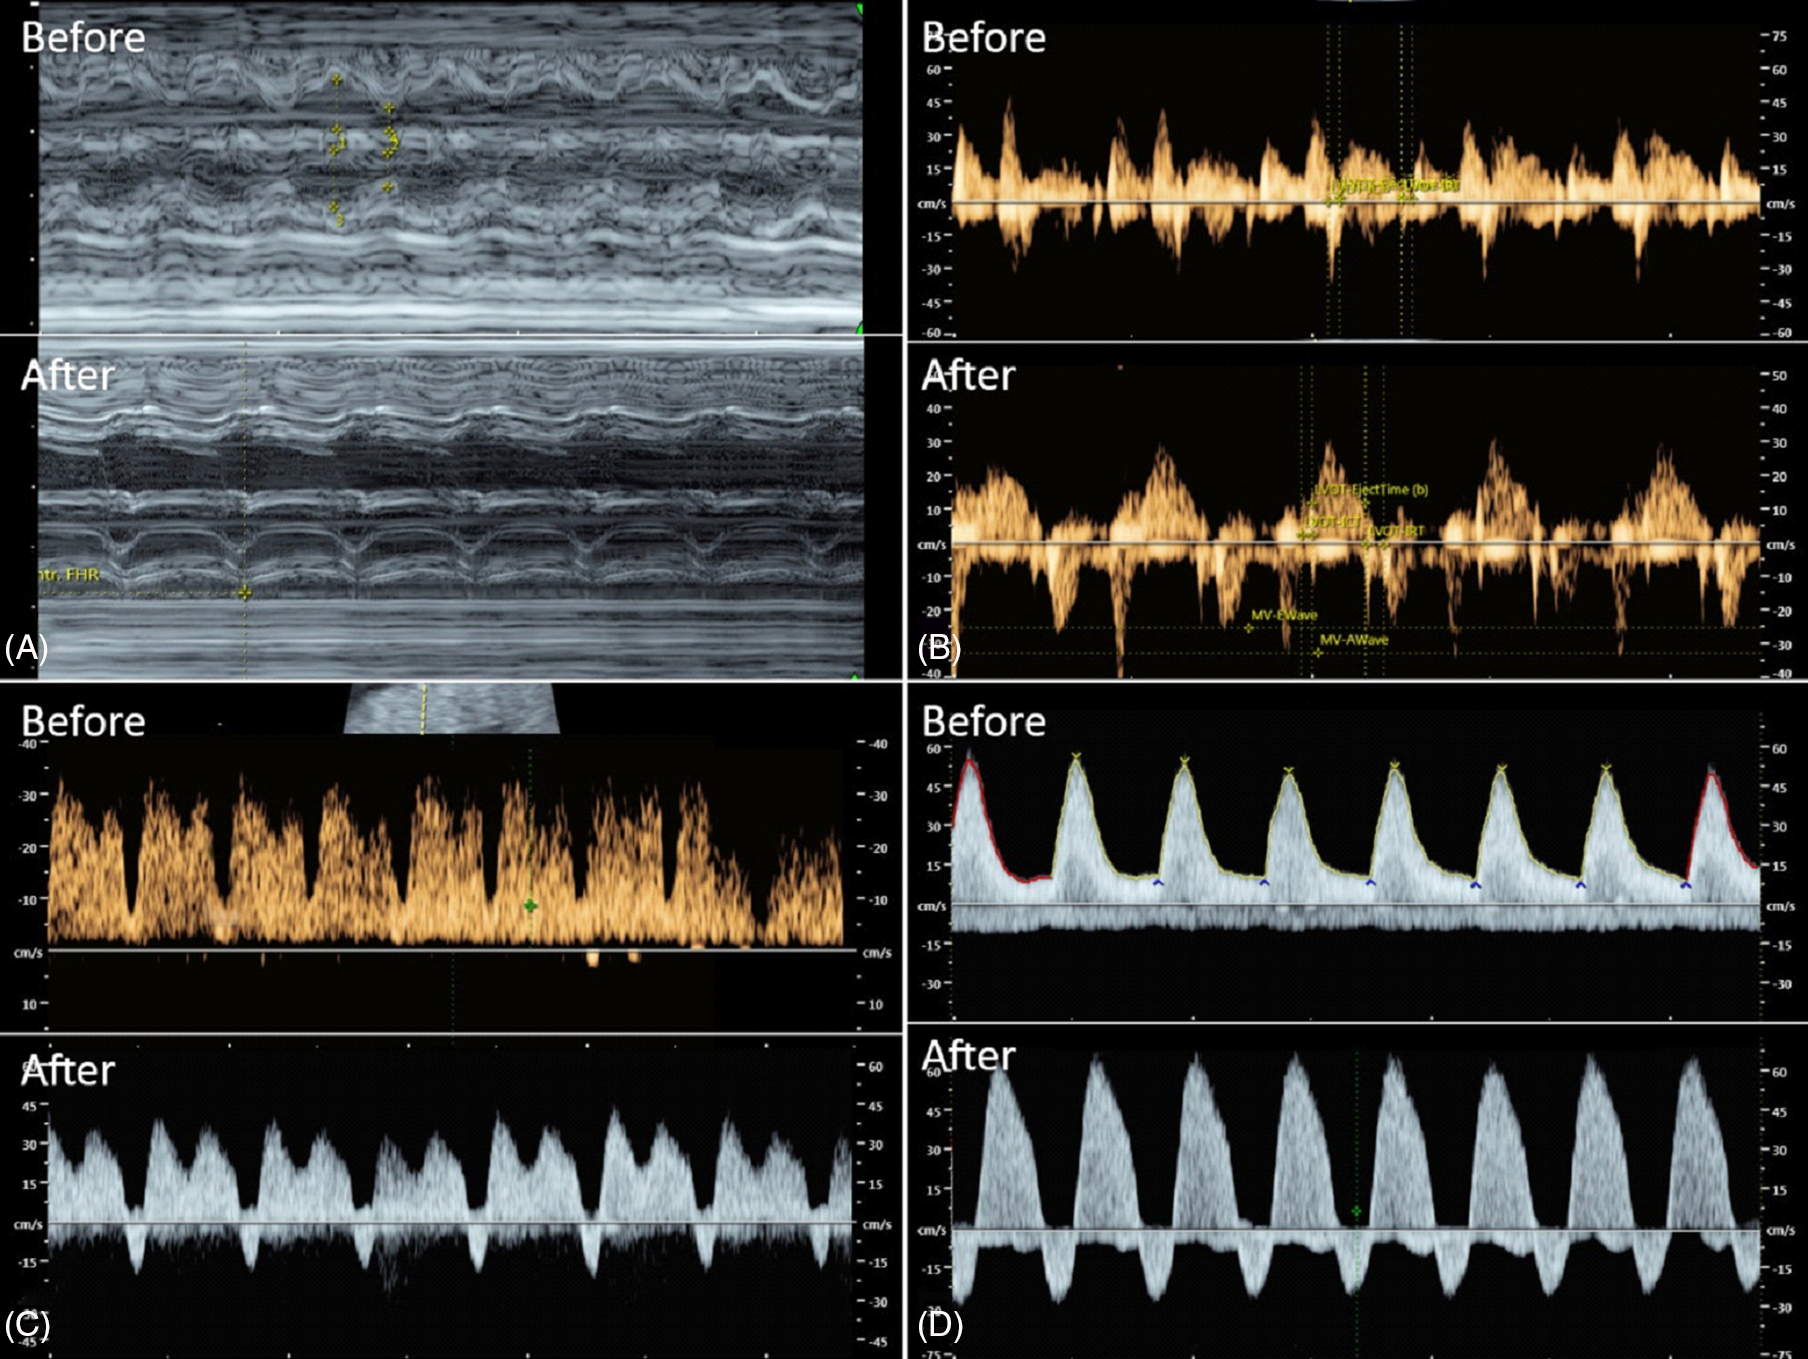

Fig. 3. Case 7 shows marked deterioration of hemodynamics shortly after the occlusive procedure (A: shortening fraction; B: Tei index; C: ductus venosus Doppler; D: umbilical artery Doppler)

In cases of preexisting compromise, as an example, case no. 7 is presented in Figure 3; the occlusion can aggravate cardiac function and deteriorate the hemodynamics leading to heart failure or even death in utero during the critical period.

In most cases, as an example, case no. 5 is presented in Figure 2 shortly after occlusion; hemodynamic changes are mainly secondary to increased volume load and pressure load, leading to an overworked heart. However, the overworked state is temporary, and the pump twin can cope with the critical situation without residual insult by an effective compensatory mechanism of fluid balance. Because there was no longer parasitic circulation, the volume load and hydropic changes prior to occlusion finally disappeared.